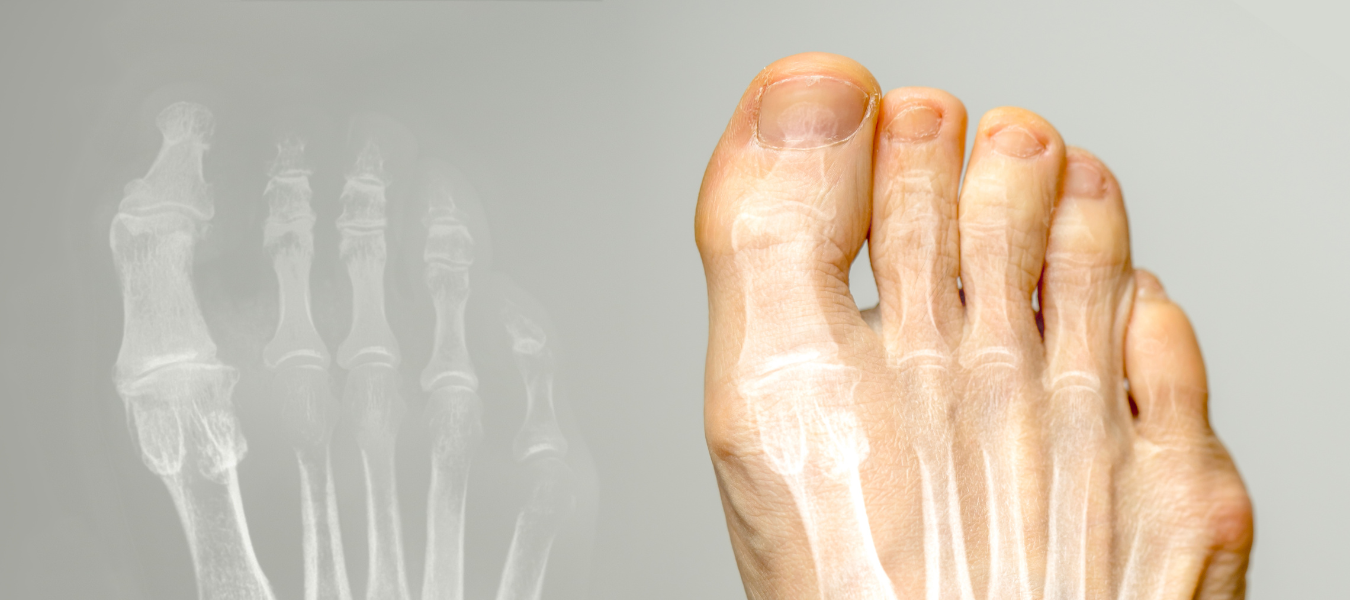

Hallux rigidus betyder "stel stortå" och innebär att du har artros i leden kring basen på stortån.Artros är en förslitning eller nedbrytning av ledbrosket inuti leden.

Efter en initial bedömning av läkare röntgas foten för att säkerställa att det handlar om artros, och i så fall kan Hallux rigidus bedömas. Du får därefter rådgivning om lindring eller behandling i just ditt fall.